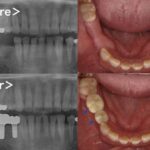

こちらが抜歯後、3ヶ月のレントゲン写真になります。

術前後のCT画像がこちらになります。3mm以下であった骨の厚みが10mm程度に増加しております。

被せ物が出来上がってきたので微調整を行い、口腔内にセットしました。

術後2年ほど経過していますが、インプラントは十分な骨でしっかり固定されており、問題なく何でも噛める状態です。長期間に及ぶ治療でしたが、患者様はとても満足されています。